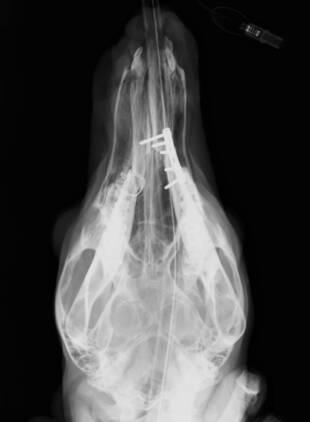

カンガルーの顎の治療 更新日:2019.10.24

カンガルーの顎の治療